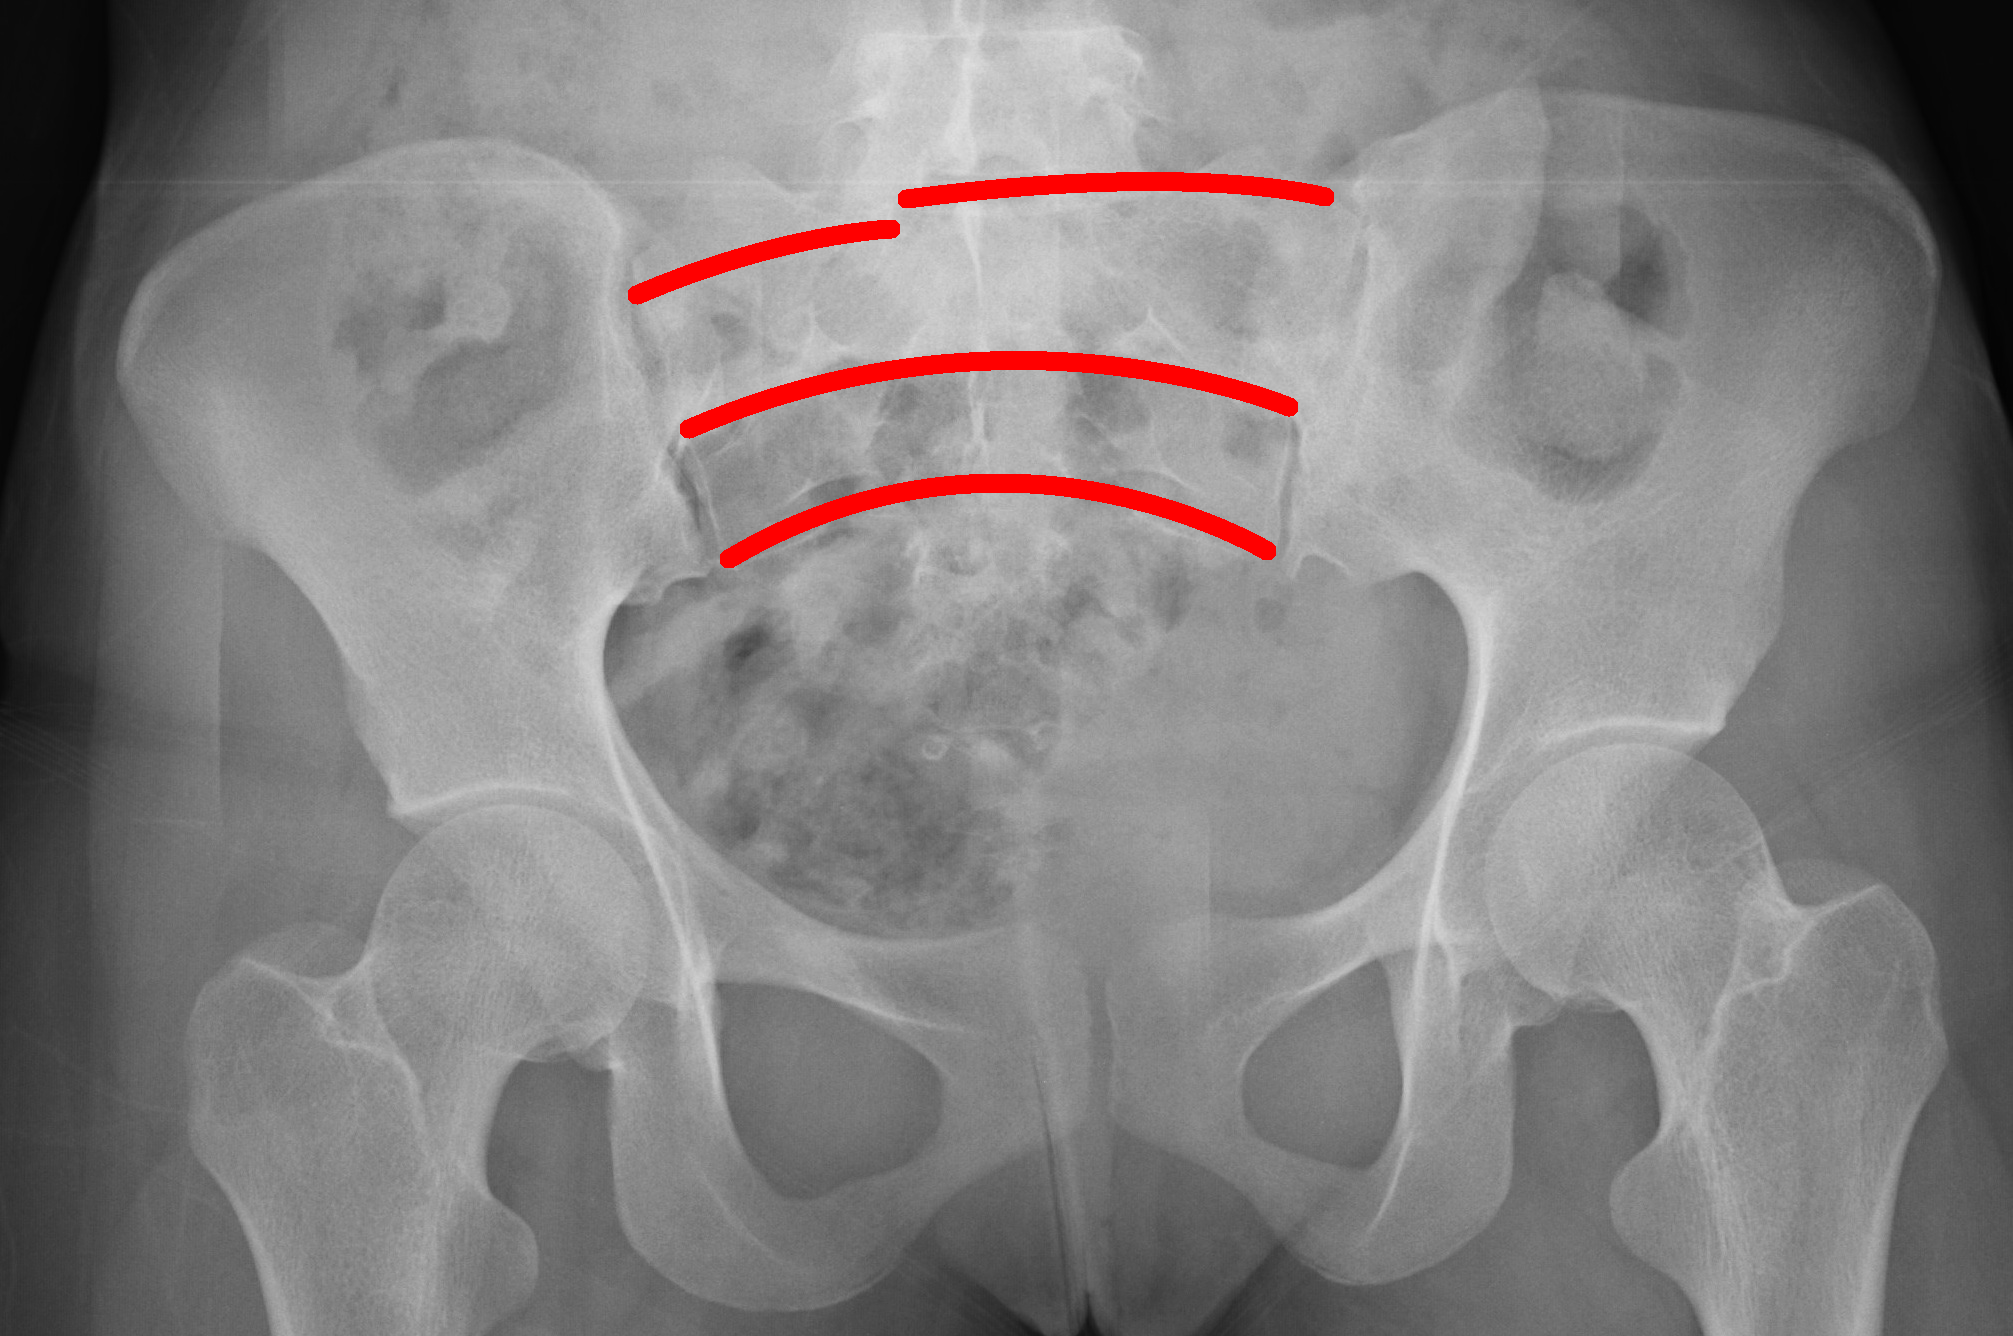

Sacral Fracture

Sacral fractures can be diagnosed when disruption of the arcuate lines are noticed on plain films.